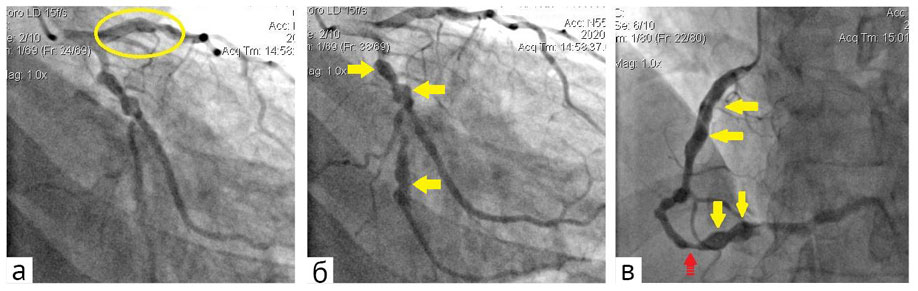

На коронарной ангиограмме (рис. 3) на 3-и сутки госпитализации: передняя межжелудочковая ветвь — аневризматическое расширение проксимального сегмента; диагональная ветвь — стеноз устья 90%; огибающая ветвь — аневризматическое расширение проксимального и медиального сегментов; правая КА — аневризматическое расширение на всём протяжении, стеноз медиального сегмента 60%; тип кровообращения — правый.

Рис. 3. Коронарная ангиография: а — аневризматическое расширение проксимального сегмента передней межжелудочковой ветви (в овале); б — аневризматическое расширение проксимального и медиального сегментов огибающей ветви (сплошные стрелки); в — аневризматическое расширение на всём протяжении (сплошные стрелки), стеноз медиального сегмента 60% (пунктирная стрелка) правой коронарной артерии

Полученные при КТ результаты определили необходимость проведения коронарной ангиографии. Её данные позволили уточнить количество, расположение и степень выраженности стенотических изменений в КА, а также определить другие локализации аневризм коронарного русла. Суммарные данные двух исследований позволили установить, что у пациента параллельно существуют как стенозирующий атеросклероз КА, так и множественные аневризмы отдельных артерий.

Сопоставление результатов коронарной ангиографии и КТ показывает, что оба патологических процесса в основном сосуществуют и развиваются параллельно в правой КА и двух ветвях левой КА. Основные ветви левой КА оказываются поражёнными различными патологическими процессами: в передней межжелудочковой ветви аневризма проксимального сегмента и данные за стеноз до 55%, в огибающей ветви аневризма с тромбозом полости и данные за стеноз до 65%, в диагональной ветви стеноз устья до 90%. Следует отметить, что стенозирование передней межжелудочковой ветви и огибающей ветви 55–65% было выявлено по результатам КТ, но не подтвердилось при коронарной ангиографии.